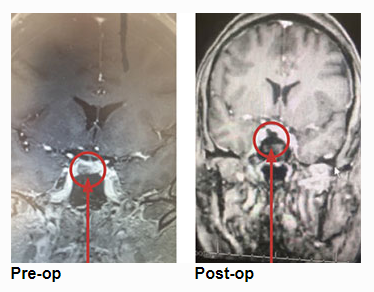

She underwent endoscopic transsphenoidal removal of the pituitary tumor, performed by Dr. Michael Brisman. Postoperative imaging showed the tumor was removed completely. Postoperative lab tests showed very low serum cortisol levels, consistent with a successful operation. She was placed on replacement hydrocortisone. She was feeling much beer, and her hypertension and diabetes were much improved. It is expected that she is cured of her Cushing’s Disease. She will undergo periodic follow-up imaging and lab tests.

This is a 46-year-old woman who presented with a 9 mm right-sided pituitary adenoma with a recent diagnosis of Cushing’s Disease. For two years she noticed some swelling of her body. The swelling was much more noticeable recently. She had pronounced swelling of her face, body, and legs. She was also recently diagnosed with hypertension and diabetes. She also had some recent impairment of her memory and thought processes. Her endocrine testing was consistent with Cushing’s Disease, that is, a pituitary source of her high systemic cortisol levels.